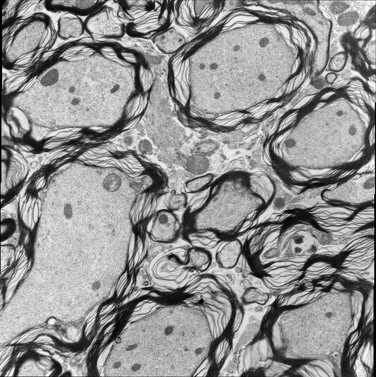

For image analogies based image registration, I have corresponding TEM/Confocal Microscopic image pairs of mouse brains with corresponding regions highlighted by a box. Using the correlative microscopy technique on the mouse brain, I want to localize specific brain regions associated with Pelizaeus-Merzbacher Disease (PMD) and do quantitative assessment of hypomyelination and demyelination in mice. PMD is one of a group of genetic disorders characterized by progressive degeneration of the white matter of the brain affecting the myelin sheath, the fatty covering that acts as an insulator on nerve fibers in the central nervous system.

The confocal microscopy images are multichannel color images in our test dataset. The blue channel is based on the blue stain DAPI (a fluorescent stain) which stains the DNA of the cell nucleus and corresponds to dark regions within the nuclei in the TEM. The green channel is based on the stains of the myelin sheats, visible as dark black layers covering the neurons in the TEM images. The red channel is not explicitly stained for and is caused by the auto-fluorescent effect of lipofuscin. The confocal image with RGB channels and its corresponding TEM image are shown in Fig. 5.

Currently I have six pairs of 2D TEM/confocal images with resolutions 582.24 pixels per μm𝜇𝑚\mu m and 7.5887.5887.588 pixels per μm𝜇𝑚\mu m respectively (1μm=1micron=106m1𝜇𝑚1𝑚𝑖𝑐𝑟𝑜𝑛superscript106𝑚1\,\mu m=1\,micron=10^{-6}\,m). The resolution is different between two images and only a small region in the confocal image corresponds to the TEM image.

Refer to caption

(a) Red channel of confocal image

(b) Green channel of confocal image

(c) Blue channel of confocal image

(d) Grayscale of confocal image

(e) Confocal image

(f) TEM image

Figure 5: Example of Confocal image with RGB channels and TEM image